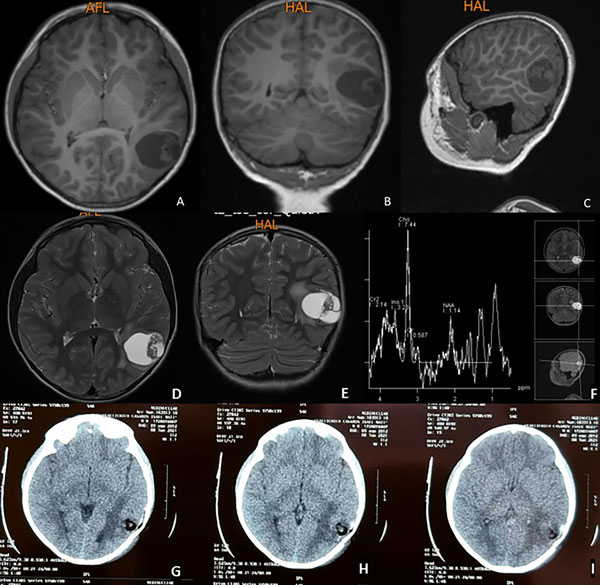

Paciente masculino de 8 años sin antecedentes patológicos conocidos, con crisis convulsivas tonicoclónicas generalizadas de 20 segundos de duración, sin presencia de aura ni relajación de esfínteres (estado postictal de 1 minuto y recuperación completa) de 2 meses de evolución. En un inicio los episodios tenían una frecuencia de 2 por semana, para alcanzar en los últimos 15 días 4 crisis diarias. A la consulta se indica levetiracetam con buena respuesta y se realiza resonancia magnética que evidencia lesión intraaxial temporal izquierda quística, hipointensa en T1 e hiperintensa en T2 y FLAIR con nódulo en su interior. La lesión mide aproximadamente 4 cm de diámetro mayor con escaso edema perilesional y moderado efecto de masa, sin herniación subfalcial y cisternas de la base visibles. La espectroscopia demostró presencia de picos de colina (Figura 1).

Figura 1. Resonancia magnética simple en secuencia T1. Se evidencia lesión ocupativa de espacio intraaxial temporal izquierda, quística, corticosubcortical hipointensa. A) Corte axial. B) Corte coronal. C) Corte sagital. En secuencias T2: D) Corte axial E) Corte coronal. F) Espectroscopía cerebral con pico de colina. G, H, I) Tomografía axial computarizada postquirúrgica: se evidencia estigma de craneotomía temporal izquierda, resección tumoral completa, lecho tumoral sin sangrado con material de hemostasia, escaso neumoencéfalo y moderado edema vasogénico.